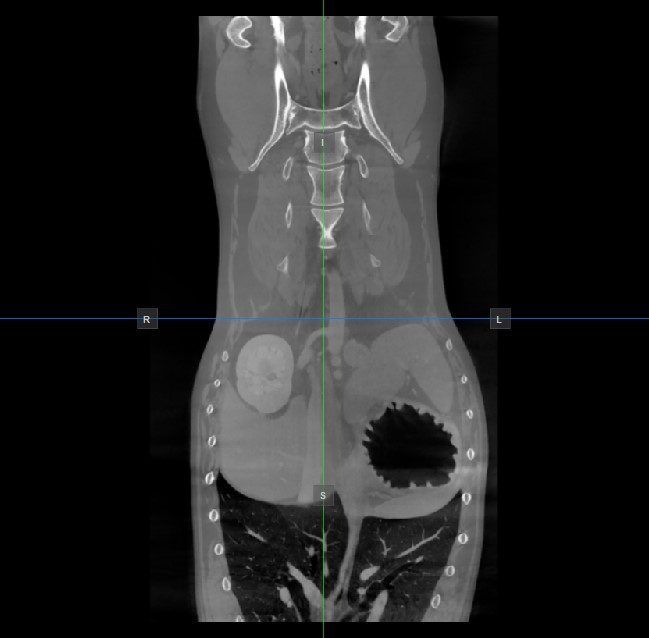

Az aktív nézetablakban nem látható másik két kép síkjának helyzetét és metszését két függőleges és vízszintes vonal jelzi, amelyeket szeletelőknek nevezünk. Minden szeletelő végpontját egy betű jelöli, amely a 3D térfogat megfelelő irányának/oldalának felel meg az RAS koordinátarendszer alapján.

Az elérhető hat oldalból csak négy van jelölve minden 2D nézetablakon. A címkék és a hozzájuk tartozó oldalak a következők:

Beteg jobb oldala (R), a test jobb oldalát jelöli

Beteg bal oldala (L), a test bal oldalát jelöli

Elülső (A), a test elülső oldalát jelöli

Hátsó (P), a test hátsó oldalát jelöli

Felső (S), a test felső oldalát jelöli

Alsó (I), a test alsó oldalát jelöli